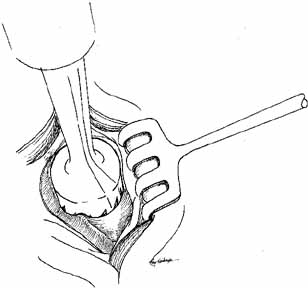

and cautery of the base.  Fig. 32 Cheesewiring of the lower canaliculus secondary to the tubing loop being

tied to tightly. It also can occur if the tubing loop is left in place

for too long in a rapidly growing child. Fig. 32 Cheesewiring of the lower canaliculus secondary to the tubing loop being

tied to tightly. It also can occur if the tubing loop is left in place

for too long in a rapidly growing child.

|